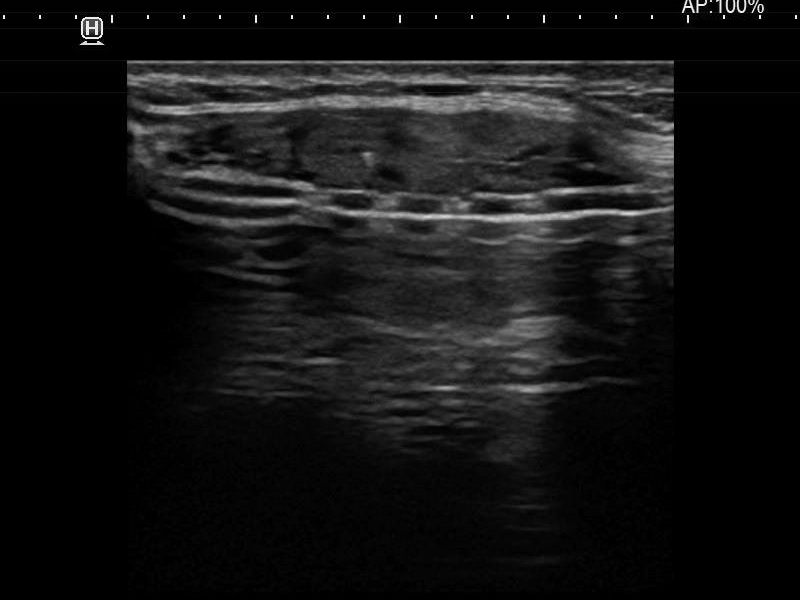

Ultrasonography. The thyroid was moderately hypoechoic and presented with numerous more and less hypoechoic discrete lesions. The largest of the latter was in the lower ventromedial part of the left lobe and had cystic areas and intranodular echogenic figures. The latter included typical comet tail artifacts, back wall cystic figures and some ambiguous small bright granules. The lesion showed both perinodular and intranodular vascularity. Compared with the former examination the nodule increased by 22% in volume. This difference is within the intraobserver variation.

Comment. Based on the presence of typical comet-tail artifacts, the questionable punctate echogenic granules are worth considering also colloid crystals.